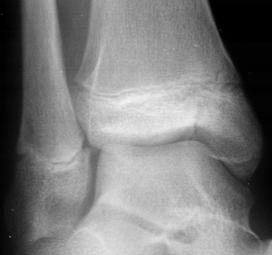

TRAUMATISMELE EXTREMITATILOR

Fracturi simple: SPIRALA OBLICA TRANSVERSALA

Fractura spirala de Fractura transversa de diafiza femurala Fractura spirala de diafiza tibiala

diafiza humerala

Fractura spirala de diafiza tibiala Fractura oblica de diafiza tibiala Fractura transversala de diafiza tibiala

Fracturi cominutive

Fracturi spirala cominutive de Fractura complexa de diafiza radiala diafiza humerala

Fractura multisegmentara intertrohanteriana Fractura Salter - Harris I

Fractura Salter - Harris I Fractura Salter - Harris II

Fractura Salter - Harris III

Fractura Salter - Harris IV Fractura Salter - Harris V